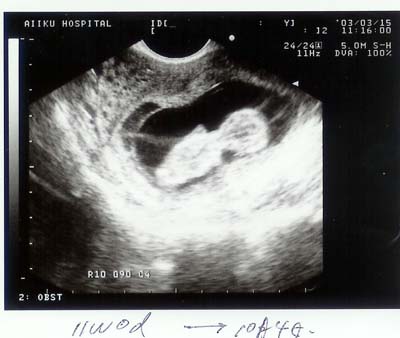

診察終了、順調だって。

人型がはっきりわかります。 |